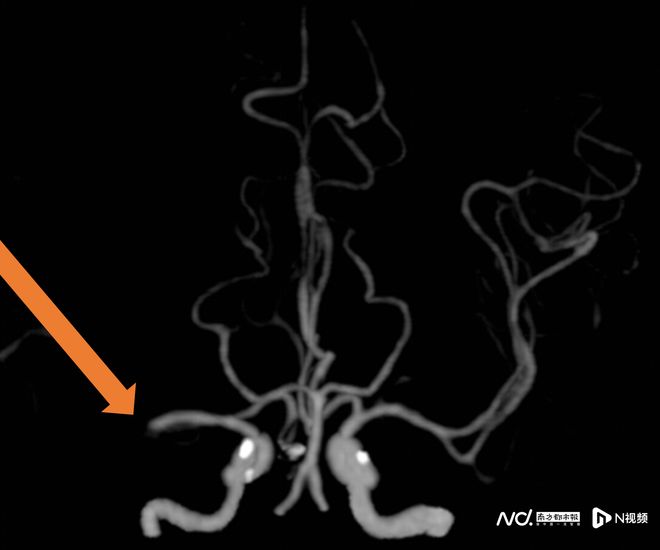

57歲的王阿姨患有風心病,一天吃飯時突然言語不清、左側肢體無力無法站起。家人立即撥打120,經卒中綠色通道確診為右大腦中動脈閉塞,隨即進行靜脈溶栓。